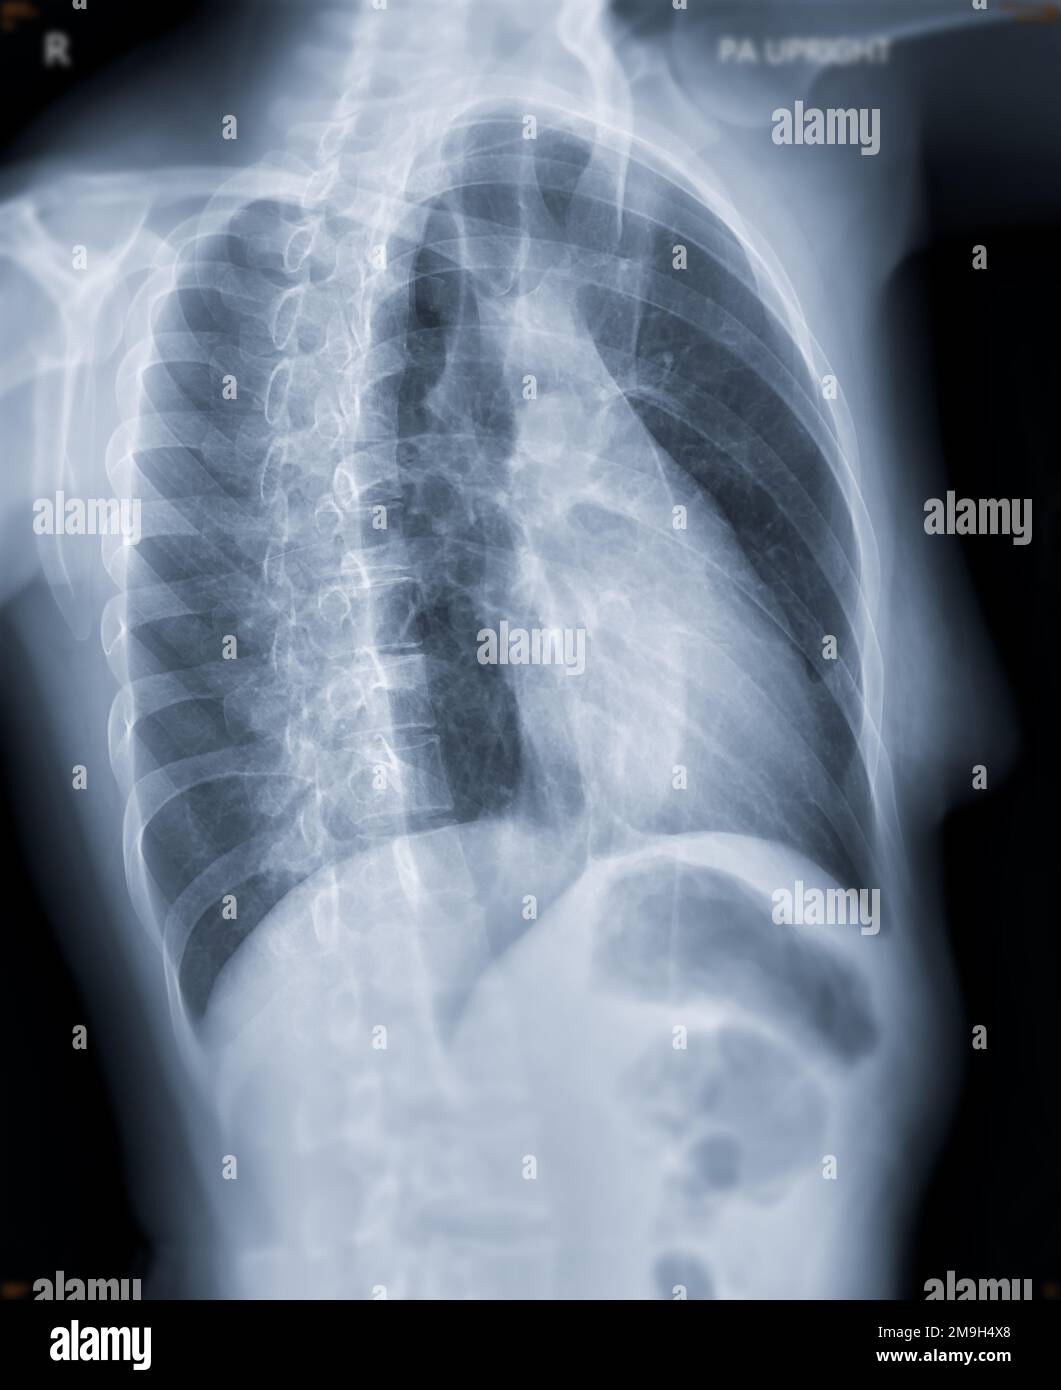

What Is A Pa X-Ray . See examples of pa and lateral views, silhouette sign, azygo. The difference between chest posterior anterior (pa) and anterior posterior (ap) radiographs. Pa is the standard projection that shows the heart size. Erect pa projections are considered the ‘gold. On the pa view, the cardiac borders are smaller and more defined. Cxr consists of two views (pa and lateral) at 90 degrees from each other. Which one is ap and which one is pa?

Which one is ap and which one is pa? On the pa view, the cardiac borders are smaller and more defined. Pa is the standard projection that shows the heart size. Erect pa projections are considered the ‘gold. See examples of pa and lateral views, silhouette sign, azygo. The difference between chest posterior anterior (pa) and anterior posterior (ap) radiographs. Cxr consists of two views (pa and lateral) at 90 degrees from each other.